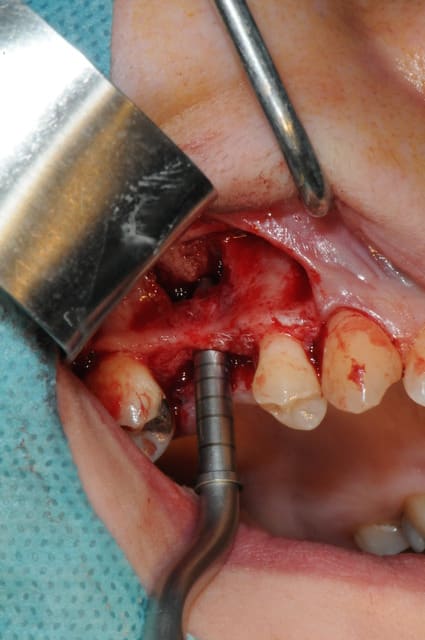

le sujet tombe à pic!

je viens de faire un sinus lift ce matin;

- 3 à 4 mm de hauteur sous sinusienne

- des cloisons de refend partout

- comblement avec du Vital Os

- un implant Axiom D4 L 10

comme je n'avais pas le temps de faire des photos la dernière fois et que j'en étais frustré, je me suis un peu lâcher aujourd'hui...

les premières photos, c'était ouverture par voie latérale

- forage et transperçage de la crête sans aller trop loin...

- essayage pilier pour parallélisme

- forage à 3mm

- visualisation de la hauteur sous la membrane de Schneider

- utilisation d'un ostéotome diamètre 3.4 puis 3.8

(sous dimensionnement de diamètre par rapport à l'implant prévu :4mm)